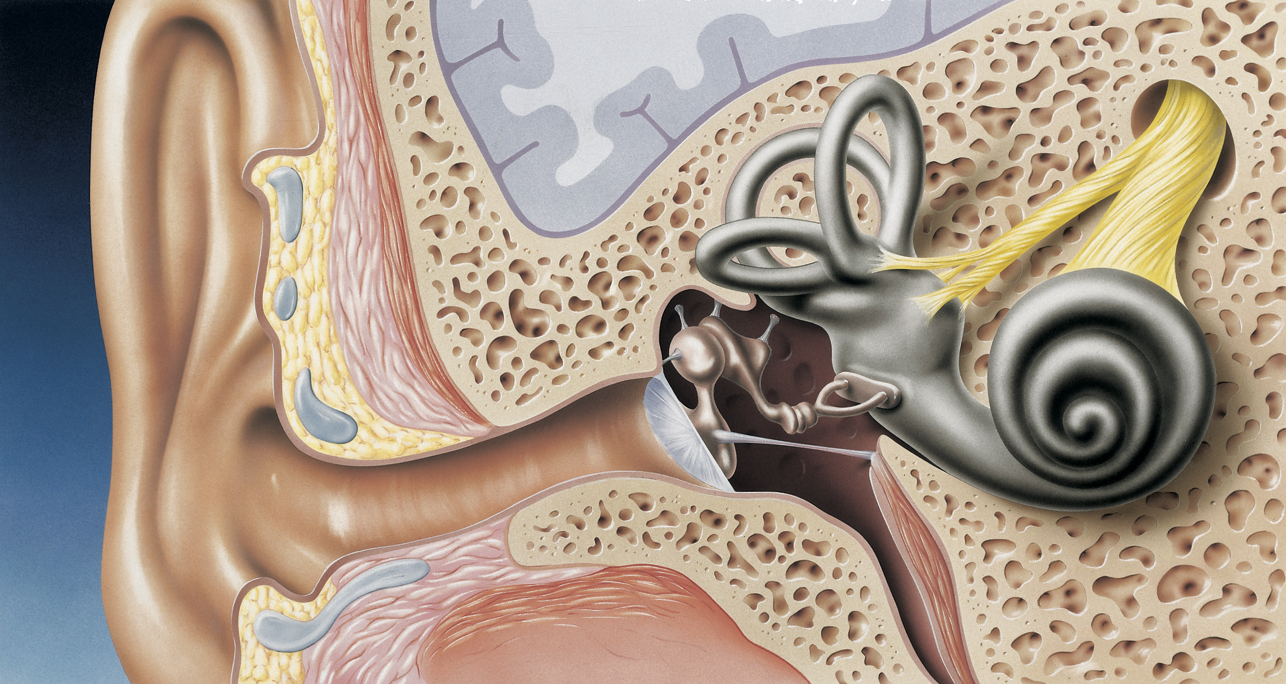

Как отмечается, нарушения слуха диагностируются у 3,5 % взрослого населения и у 2% детей. Зачастую это генетические нарушения, одна из причин которых, — неправильно подобранные антибиотики. Эти препараты провоцируют мутации m.1555A>G — замену аденина на гуанин в 1555 позиции гена MT-RNR1, кодирующем митохондриальную рибосомальную РНК. И связана мутация с высоким риском потери слуха.

Предложенный тест MT-RNR1, получивший название гена, основан на технологии LAMP — петлевой изотермической амплификации. С помощью теста провели серию доклинических исследований с участием 159 новорожденных, при этом доля правильно определённых положительных резултьтатов составила 100%. Время анализа заняло 26 минут.